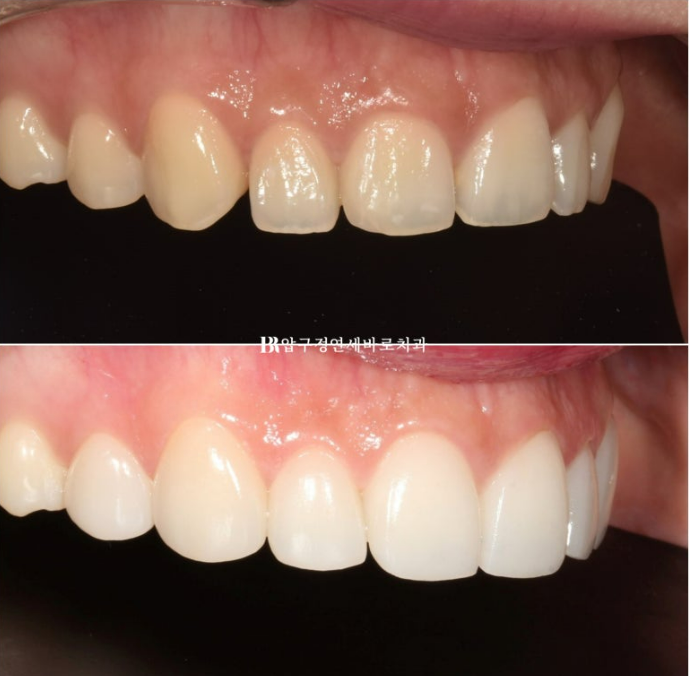

치아 사이 벌어진 공간은 라미네이트로 메꿔졌습니다.

송곳니는 기존 치아 길이를 최대한 유지하고 측절치에서 앞니로 갈수록 세로로 점점 더 길어지게 제작하여 아래로 둥근 곡선의 스마일라인을 재현합니다.

정면 비포 애프터 사진을 보면 스마일라인 변화가 좀 더 잘 보입니다.

스마일라인을 그어볼까요?

자연스러운 스마일라인은 인상을 바꿔줍니다.

아랫입술과 평행한 스마일라인

위에만 무삭제 라미네이트를 하면 아랫니와 색상 차이가 심할까봐 걱정하시는 분들이 많습니다.

환자분 본연의 치아 색에 따라 다르지만 본래 치아가 어둡지 않은 분은 아랫니에 미백치료만 해도 톤차이가 거의 없이 잘 어울러집니다.